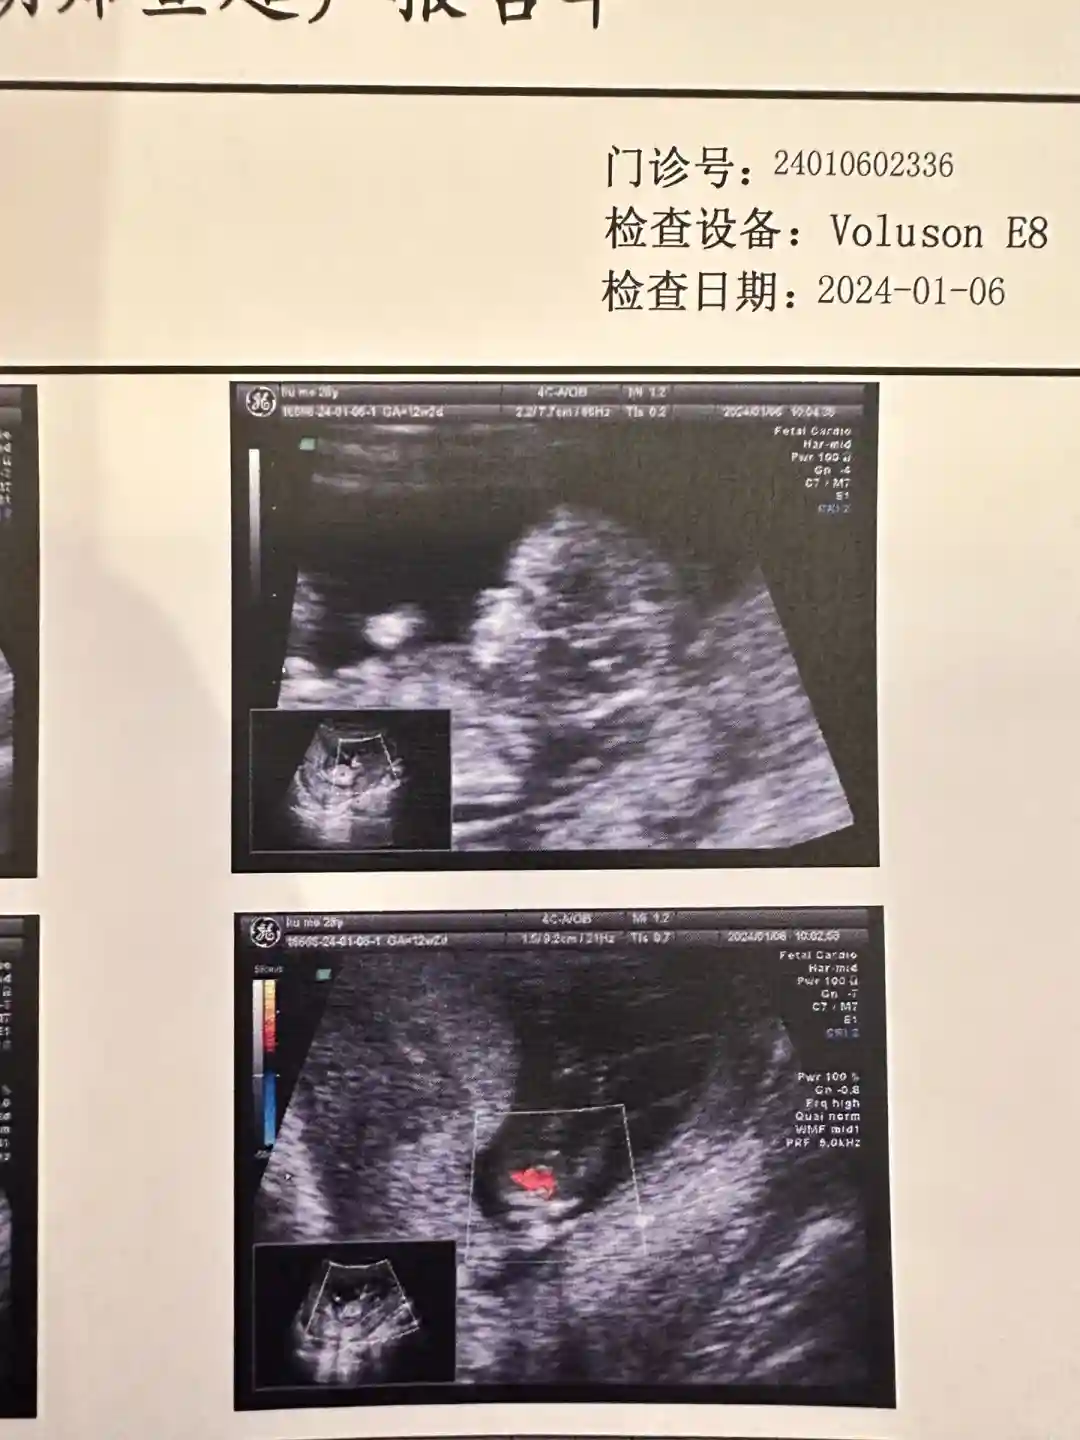

在建档前的每次B超和抽血我都是选择安琪儿的夜间门诊,这样不影响白天上班,不需要频繁请假。建档后的产检我周内去过,但大部分都是周末去的。我当时的医生是张培莲医生,张主任的门诊时间是周一四六,公众号上每周会有推送各位医生的门诊时间,很方便。第一次去的时候和销售联系好时间,全程她会带着你,非常方便。之后每次检查完医生会直接预约好下一次的产检时间,到时候直接去挂号就可以。周内人很少,我每次周六早上去人会稍微多一些,但和公立医院相比还是少很多很多的,我基本每次检查都在两个小时内搞定,家属也可以全程陪同,孩子爸爸也可以每一次都看到宝宝B超的变化。每次检查的前一天医院的工作人员会提醒,并会说需不需要空腹。所有的工作人员态度都非常好,医生的态度也是,有问必答,非常有耐心。